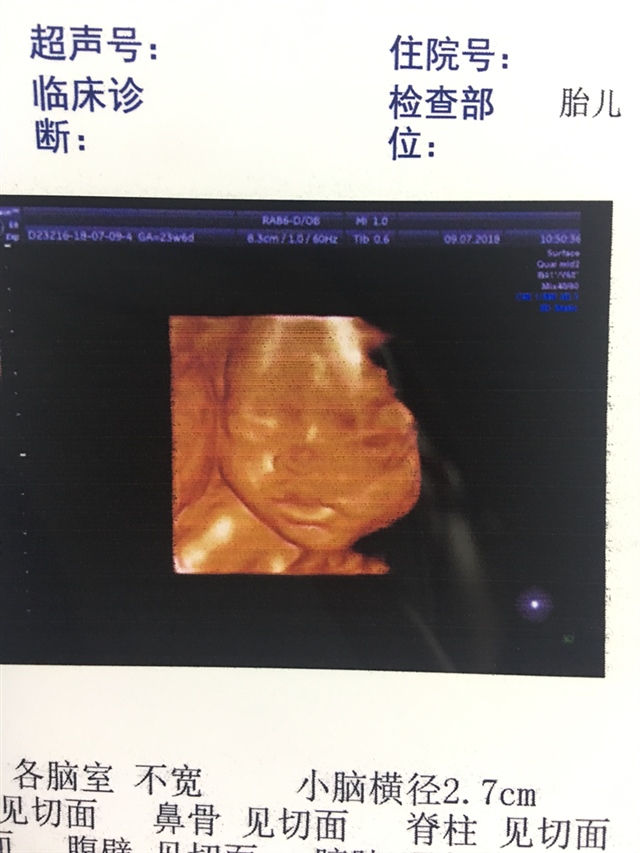

可乐双胞胎兄弟

2018-06-01

2736 人回复